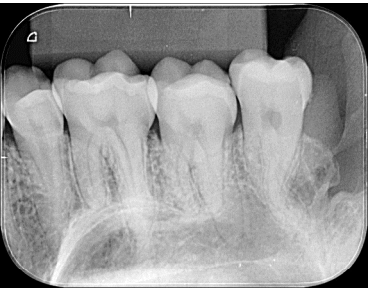

Para correta montagem de radiografias odontológicas, é necessário saber pontos anatômicos que identifiquem a posição do filme e os elementos dentários em questão.

Diante disso, analise a radiografia ilustrada e assinale a alternativa correta.